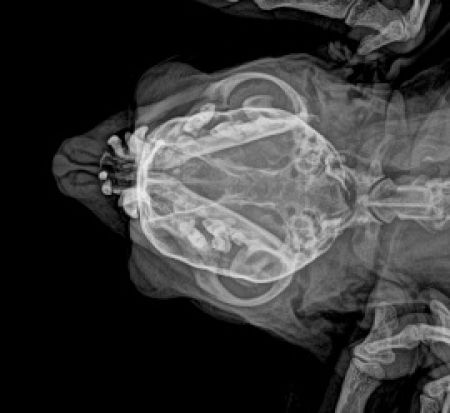

Craniu